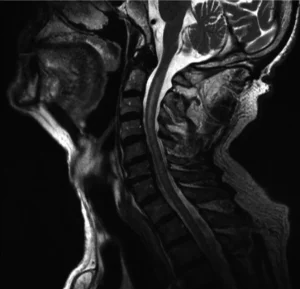

MRI (Manyetik Rezonans Görüntüleme)

MRI, miyelit tanısında önemli bir görüntüleme tekniğidir. Omurilikteki iltihaplanma ve hasar, MRI taramalarıyla net bir şekilde görülebilir. MRI, miyelit teşhisi koymada ve iltihabın yayılma derecesini belirlemede kullanılır.